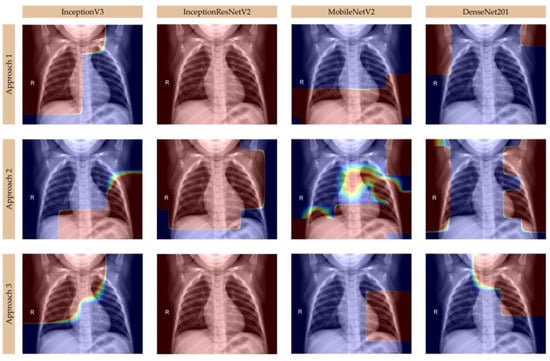

Moreover, we analyzed Grad-CAM visualizations for deep learning models—InceptionV3, InceptionResNetV2, MobileNetV2, and DenseNet201—in classifying healthy lungs, viral pneumonia, and bacterial pneumonia from chest X-ray images, using multiple Grad-CAM approaches to highlight key decision-making areas, as presented in Figure 4, Figure 5, and Figure 6, respectively. In healthy cases, models like InceptionV3 and DenseNet201 show minimal activation, primarily along the ribcage or lung periphery, while viral pneumonia is characterized by diffuse, bilateral activation across both lungs, often including the heart region [,], as seen in MobileNetV2 and DenseNet201, which effectively capture interstitial changes. Bacterial pneumonia, in contrast, is identified by sharp, localized activation, typically within one lung lobe [], with DenseNet201 excelling in its detection due to its highly focused heatmaps, while InceptionResNetV2 also well differentiates the sharply defined activations in specific lobes. Grad-CAM approaches, particularly Approach 3, provide the clearest visualizations, revealing sharp, focused bacterial pneumonia regions and broader, generalized viral patterns, while Approach 1 highlights initial lung field activations, and Approach 2 refines distinctions between pneumonia types. MobileNetV2 performs best for viral pneumonia due to its strong central lung and heart activation, DenseNet201 is the most accurate for bacterial pneumonia, with its distinct lobar focus, and InceptionResNetV2 offers a balanced performance for both. Key takeaways include minimal activation in healthy cases, diffuse patterns in viral pneumonia, and localized, sharp activations in bacterial pneumonia, with DenseNet201 emerging as the most precise model for distinguishing between the two pneumonia types [,]. Overall, Grad-CAM effectively illustrates how these models interpret pneumonia patterns, confirming DenseNet201’s superiority for bacterial pneumonia and MobileNetV2’s strength in viral pneumonia detection.

Figure 4.

Grad-CAM visualizations for healthy lungs.

Figure 5.

Grad-CAM visualizations for viral pneumonia.

Figure 6.

Grad-CAM visualizations for bacterial pneumonia.